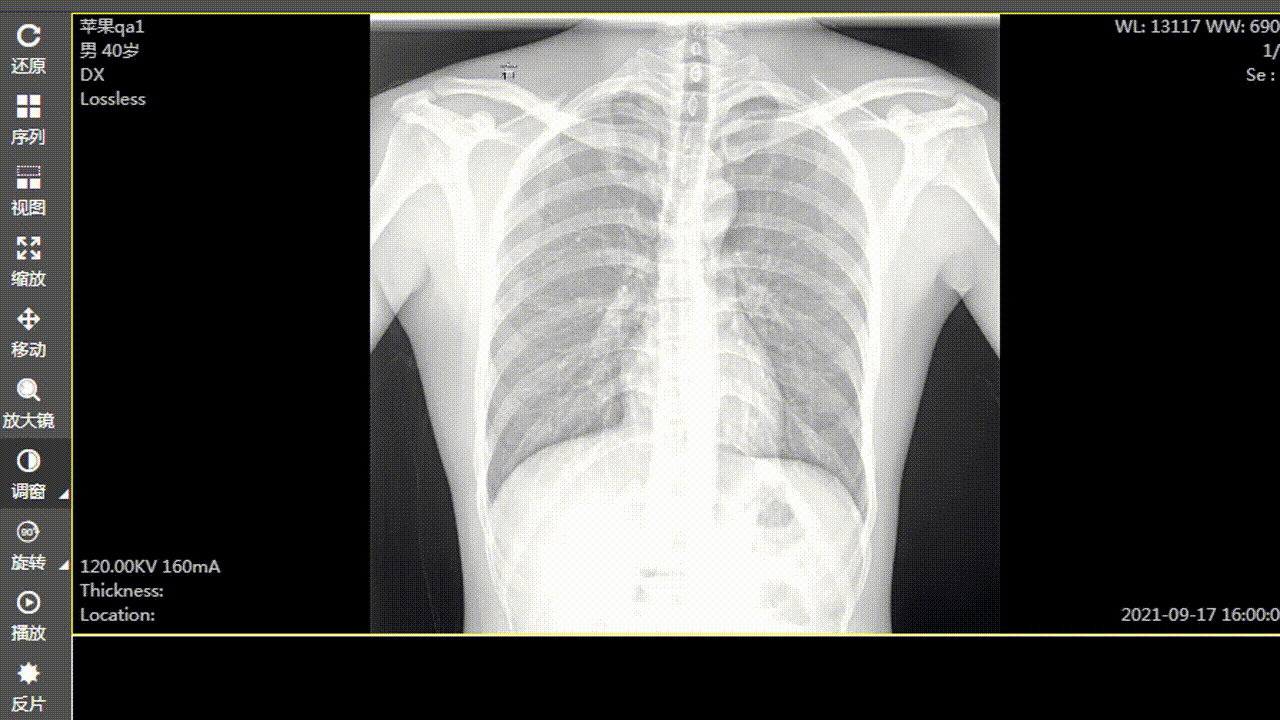

​ 在 web 版阅片器(图像显示工具)的开发工程中发现,在对 dr、dx 这种大图(图像普遍是 2000px 左右宽高的图像,每个像素大小是 16 位或者 32 位的)进行调窗时,浏览器直接卡死,图像显示变化有很大延迟。后来查阅资料,使用 gpujs 来实现调窗时图像的处理,结果:调窗时图像显示变化变得比较线性,性能估计提升 5/6 倍,能满足业务需求。当然,图像的一些高级处理,都是可以用 gpujs 来实现,调窗只是一个点。

1.gif ​ 使用后效果:

2.gif